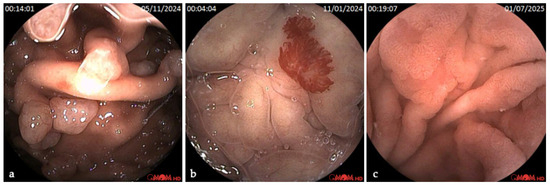

Background/Objectives: Robotic capsule endoscopy (RCE) is an emerging technology that combines magnetically controlled gastric navigation with conventional capsule enteroscopy (CE), enabling a minimally invasive, comprehensive evaluation of the upper- and mid-gastrointestinal tract. This study aimed to characterize the real-world implementation and diagnostic [...] Read more.

Background/Objectives: Robotic capsule endoscopy (RCE) is an emerging technology that combines magnetically controlled gastric navigation with conventional capsule enteroscopy (CE), enabling a minimally invasive, comprehensive evaluation of the upper- and mid-gastrointestinal tract. This study aimed to characterize the real-world implementation and diagnostic performance of RCE in a European tertiary referral center. Methods: A retrospective, single-center analysis was conducted on adult patients (≥18 years) who underwent RCE (Omom RC) between June 2023 and July 2025. Eligible patients had a clinical indication for small bowel CE and a concurrent requirement for diagnostic gastroscopy or reassessment of known gastric lesions. The RCE protocol comprised an initial robotic-guided gastric examination followed by passive transit through the small bowel. Results: A total of 85 patients were included (52% female), with a median age of 49 years (IQR 40–64). The most common indications were suspected or established inflammatory bowel disease (57%) and iron deficiency anemia (31%). Gastric preparation was rated at least fair in 98% of cases, with good preparation in 38%. Median gastric transit time was 74 min (IQR 35–106). Relevant gastric findings were identified in 39 cases (46%), namely polyps (18%) and angiectasias (8%, including one with active bleeding), in addition to signs of chronic gastritis. Thirteen patients underwent subsequent endoscopy, resulting in seven therapeutic procedures. Small bowel findings were present in 60 patients (71%), including P3 (active bleeding) in 3% and P2 lesions (angiectasias, ulcers, tumors, varices) in 39%. One moderate adverse event occurred: small bowel capsule retention in a patient with multifocal neuroendocrine tumor and ileostomy, requiring endoscopic intervention. Conclusions: Robotic capsule endoscopy is a feasible tool for dual-region gastrointestinal evaluation. It enables high-quality gastric visualization, facilitates early detection of clinically actionable lesions, and maintains the diagnostic yield expected from standard small bowel CE. These findings support the integration of RCE into diagnostic pathways for patients requiring simultaneous gastric and small bowel assessment. Full article

Show Figures

Figure 1